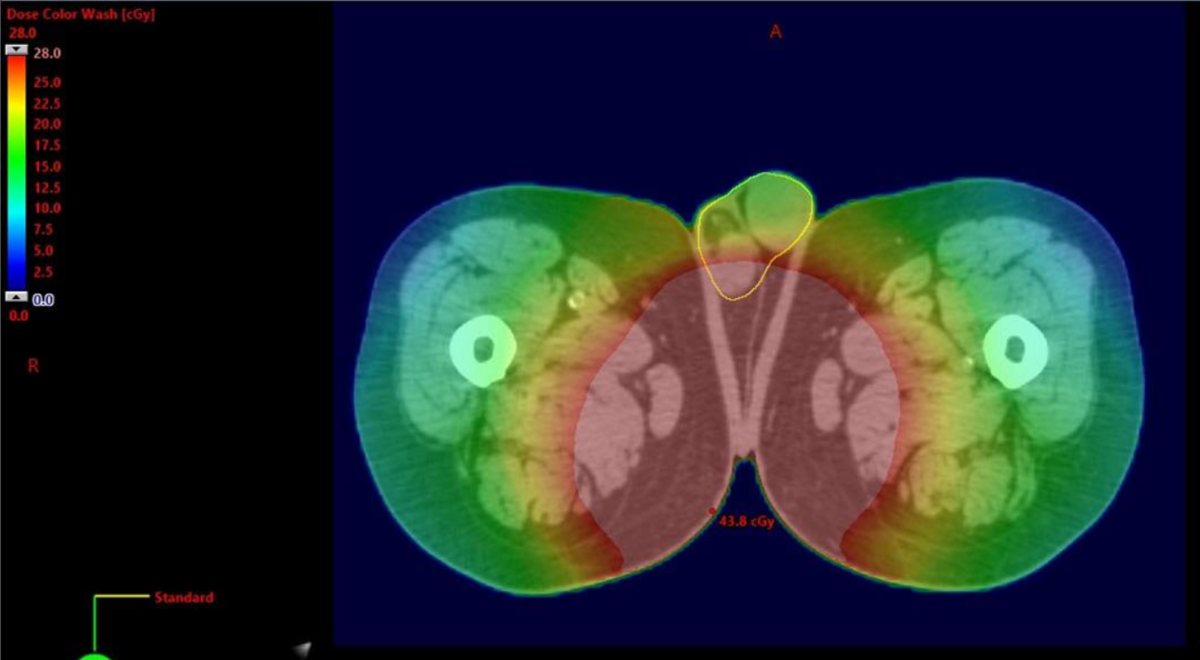

Thus, I decided to test my imagination. I happened to be reviewing a prostate plan today (high risk with terrible urinary function, so going to 79.2), and told my physicist about this discussion. I contoured the testicles (quickly and without breaking it down into left/right) and we re-ran the plan. We put no weight on the testicles or changed the plan in any way:

1628089039900.png

1628089066157.png

I whopping mean of 27.3 cGy and a max of 58.1 cGy. Sure, this is an N=1, but everything about this patient's case and anatomy was very average, so I have to think that this is a representative dose wash.

Again, I'm pro-proton, but testicle dose/serum testosterone drop as a justification for IMPT over IMRT seems like murky water to swim in.